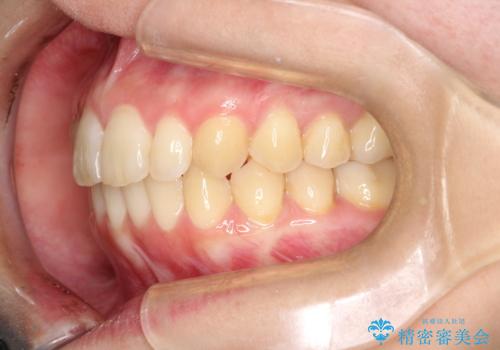

[インビザライン ライト] 短期間(3.5ヶ月)で終わるマウスピース矯正

![[インビザライン ライト] 短期間(3.5ヶ月)で終わるマウスピース矯正の症例 治療前](https://seimitsushinbi.jp/wp/wp-content/uploads/2020/02/C3-500x350.jpg?v=1580813654)

![[インビザライン ライト] 短期間(3.5ヶ月)で終わるマウスピース矯正の症例 治療後](https://seimitsushinbi.jp/wp/wp-content/uploads/2020/02/2f36cdf472a802b537022ae239b8cb6b-500x350.jpg?v=1580813669)